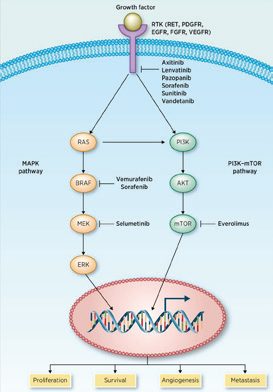

美国克利夫兰医学中心Rini等报告,Tivozanib对比索拉非尼三线或四线治疗转移性肾细胞癌,可改善无进展生存期(PFS),且耐受性更好。(Lancet Oncol. 2019年12月3日在线版)既…

美国纪念斯隆凯特琳癌症中心Lee等报告,在免疫治疗(IO)失败的转移性肾细胞癌(mRCC)患者中,约2/3的患者经VEGF抑制联合免疫检查点抑制剂治疗后有缓解。(2019 IKCS)Lenvatin…

美国加州大学的Lara和MD Anderson癌症中心的Campbell就非透明细胞型肾细胞癌(nccRCC)目前的治疗策略进行了激烈辩论。(国际肾癌研讨会IKCS 2019)ICI的优势Lara支持将免疫检…